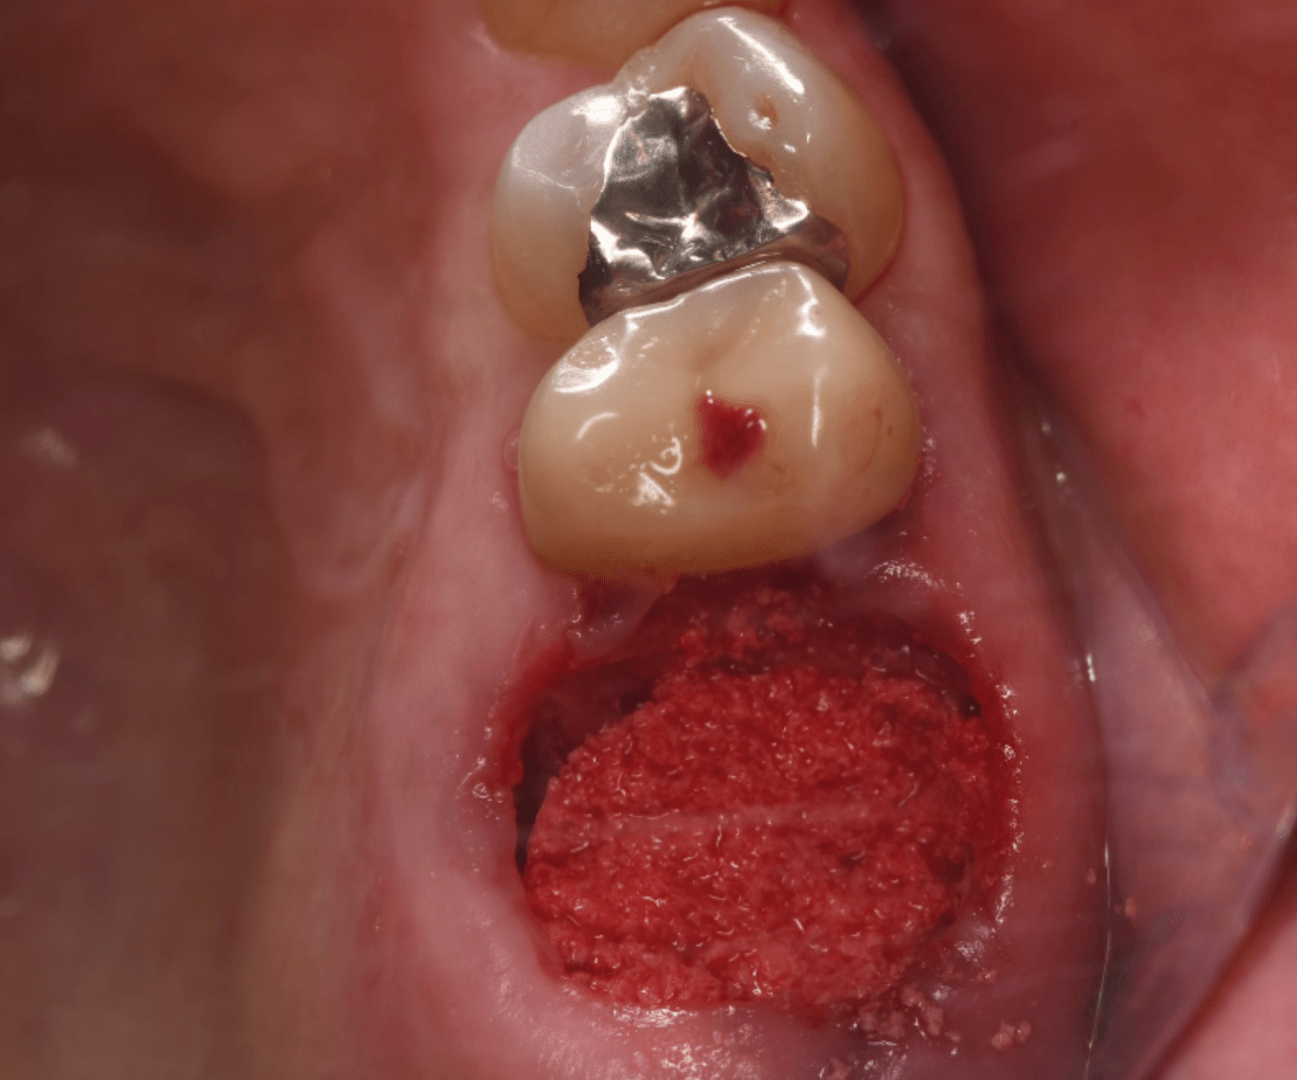

このようなケースは、抜歯時に前もって骨を足してリッジプリザベーションをしておくことにより、遥かにインプラント時に

インプラントが楽になります。もちろんインプラント時の患者負担やインプラント費用も抑えられます。

私は細菌を通さない膜で、抜歯窩に入れた骨を守っておき、約1ヶ月後に膜を外します。

感染せずに上皮が出来て、一定期間で骨ができれば成功です。あとはインプラントは楽になります。